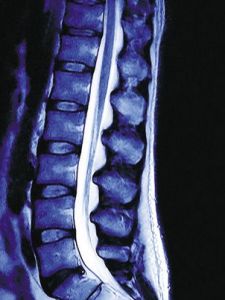

椎體良、惡性壓縮性骨折MRI診斷的優點及不足

椎體良性壓縮性骨折的原因多見於骨質疏鬆症,也可見於外傷、結核、血管瘤等。而惡性壓縮性骨折的原因多見於椎體轉移瘤,也可是椎體原發性惡性腫瘤、多發性骨髓瘤、惡性淋巴瘤、白血病等。

普通X線平片、ECT骨掃描及CT已成為診斷椎體壓縮性骨折的常規技術手段,然而在診斷及鑑別椎體良、惡性壓縮性骨折時常不夠準確。近年來,MRI已越來越多地用於評估椎體壓縮性骨折,根據壓縮椎體的信號及形態學改變,已經建立了一套較可靠的MRI診斷標準,用於鑑別椎體良、惡性壓縮性骨折。本文目的是要複習椎體良、惡性壓縮性骨折在MRI上的表現特徵,並探討磁共振在診斷及鑑別診斷上的優點及不足。

椎體惡性壓縮性骨折信號改變有:壓縮椎體信號在T1WI(自旋迴波序列)上多呈瀰漫性低信號,T2WI上呈等或高信號,壓脂相(短時間反轉恢復序列或T2WI壓脂)上呈高信號,這種信號改變可以是均勻或不均勻的,增強掃描(Gd-DTPA)可見病灶有不均勻的異常強化[1,2]。有時也可見椎體內有局灶性不規則的低信號病灶,有正常骨髓信號存在,這可能是椎體中只有部分骨髓被異常組織代替,但較少見。鄰近未壓縮的椎體及附屬檔案受侵犯時也可出現相似的信號變化,椎間隙正常。

一般認為,MRI上能夠提示惡性壓縮性骨折的形態學特徵有:椎體壓縮變扁,其後緣骨皮質呈弧形或球狀隆起,椎弓根受侵犯,椎管內硬膜外及椎旁軟組織腫塊形成。據筆者觀察的一組病例,硬膜外軟組織腫塊對診斷惡性壓縮性骨折的敏感性為81%,特異性為100%。而椎體後緣呈弧形或球狀隆起及椎弓根受侵犯則分別為75%、92%及82%、94%。

良性壓縮性骨折

良性壓縮性骨折椎體的信號改變隨骨折時間不同而有所變化。以骨質疏鬆症性壓縮性骨折為例,急性期在T1WI上的典型表現為:壓縮椎體終板骨折處附近有局灶性低信號影存在,其大小在最初2~4個月間無明顯變化,對側部分信號正常;T2WI上表現為壓縮椎體的信號與鄰近正常椎體基本相同,終板下方可見線狀低信號影,這是由於骨折線或骨小梁相互嵌插所致,增強掃描可見壓縮椎體部分或全部與鄰近正常椎體信號相同;壓脂(短時間反轉恢復或T2WI壓脂)序列上終板骨折附近有局灶性線狀或三角形高信號影,也稱液體徵,這是急性或亞急性骨質疏鬆症性壓縮性骨折的一個特徵,而惡性壓縮性骨折中很少見。

壓縮椎體有一個形態改變對良性壓縮骨折的診斷特異性很高,就是椎體後上角向後移位突向椎管,基本可達到100%,但較少見。椎體骨質疏鬆症性壓縮骨折通常沒有椎弓根受累的徵象,也沒有硬膜外腫塊形成。慢性期壓縮椎體信號在T1WI及T2WI圖像上多為正常,有時可見局限性低信號,但其餘部分信號均正常。增強掃描可見輕度不均勻的強化。

MRI的成像序列

雖然普通的成像序列(T1WI及T2WI快速自旋迴波)一般能鑑別椎體良、惡性壓縮骨折,但T2WI(不壓脂)序列在鑑別椎體急性外傷與轉移瘤所致的壓縮骨折時的作用卻很有限。而壓脂(短時間反轉恢復及T2WI壓脂)序列能夠增強正常骨髓與病變組織的信號對比,更有助於顯示病變組織。因此,上述成像序列一般作為常規使用。目前,還出現了一些新的成像技術如動態增強掃描及彌散加權用於椎體良、惡性壓縮骨折的鑑別。但由於臨床套用不多,其有效性尚待進一步驗證,此外,這些新技術對MRI的硬體要求較高,短期內推廣難度較大。

MRI檢查的優點及不足

由於MRI對壓縮椎體內的信號變化非常敏感,加上它具有多軸位成像功能及很高的軟組織解析度,因此它不僅能很好地顯示壓縮椎體的形態學及信號改變,還能很好地顯示周圍軟組織的病變。所以MRI對大多數椎體良、惡性壓縮骨折病例都能做出正確的診斷及鑑別診斷。

然而,MRI對有些疾病所致的椎體壓縮骨折的診斷作用有限,如多發性骨髓瘤,它所致的椎體壓縮性骨折在臨床上並不少見,而且多數病例呈現明顯的惡性病變進程,但其中多數病例在MRI上的表現與良性的骨質疏鬆性壓縮骨折相同,只有少數患者呈惡性壓縮性骨折的表現。因此,在鑑別非外傷性且在MRI上有良性壓縮骨折表現的病例時應注意這一點。

外傷性椎體壓縮骨折急性期在T1WI上椎體呈瀰漫性低信號,同時由於椎旁軟組織損傷(挫傷、血腫)可出現腫塊樣表現,因此容易與惡性壓縮性骨折混淆。但患者有急性外傷病史及其他徵象如椎間盤損傷、椎體骨折片及脊髓挫傷等有助於鑑別。